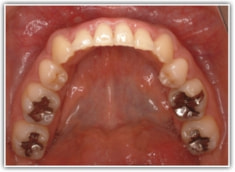

治療前

修復歯、補綴歯もあります。下顎8番が水平埋伏しています。